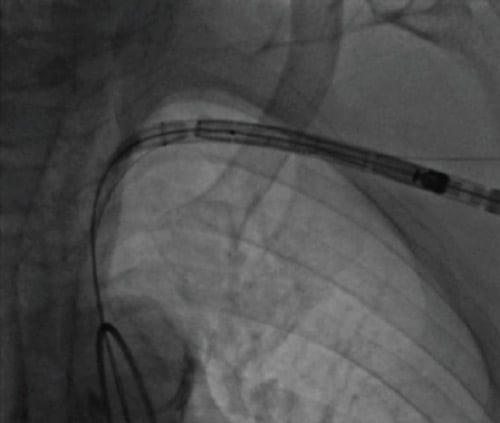

Step 6: perform TAVI “as transfemoral” once access is secured

- Proceed with valve delivery and implantation using your planned platform (Figure 9).

- Maintain coaxial alignment of the delivery and avoid traction/torsion on the axillary arteriotomy during device exchanges.

- Keep the safety channel available throughout.

Figure 9: Passage of the valve delivery from the axillary artery, through the subclavian artery into the aorta